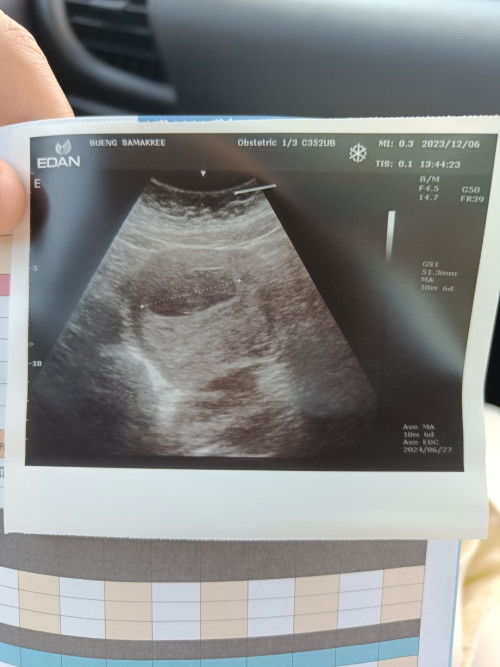

วันนี้อายุครรภ์ 6w 4d คุณหมอทำการซาวด์ครั้งแรก แต่หมอบอกว่าเจอแต่ถุงตั้งครรภ์และถุงค่อนข้างใหญ่เหมือนท้อง 10w เลย แล้วตีครรภ์ตามซาวด์ เราคิดหนักเลยกลัวจะท้องลม ไม่มีเลือดออก ไม่มีอาการแพ้รุนแรง มีเวียนหัวเหม็นกลิ่นอาหารบ้าง มีใครมีประสบการณ์ซาวด์ครั้งแรกไม่เจอน้องบ้างค่ะ แล้วเจอครั้งแรกกันตอนกี่วีค #ขอคำแนะนำหน่อยค่ะ #ท้องแรกคะ #ขอบคุณสำหรับคำตอบค่ะ